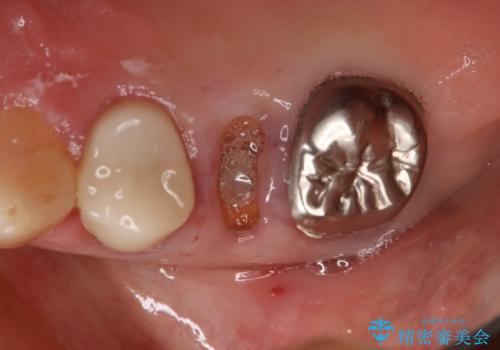

- 右上小臼歯の破折を理由に来院された患者様です。

残根状態で保存不可能と判断し、抜歯した上で補綴することを提案しました。

インプラント治療を希望されたので治療の期間・回数の少ない抜歯即時埋入インプラントでの治療を計画しました。